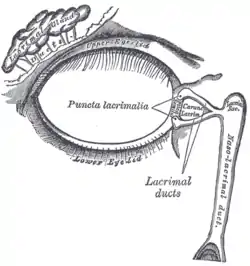

The lacrimal apparatus. Right side. Note outdated terminology: The "Lacrimal ducts" in Gray's are now called "Lacrimal canals". | |

The lacrimal punctum (pl.: puncta) or lacrimal point, is a minute opening on the summits of the lacrimal papillae, seen on the margins of the eyelids at the lateral extremity of the lacrimal lake. There are two lacrimal puncta in the medial (inside) portion of each eyelid. Normally, the puncta dip into the lacrimal lake.

Together, they function to collect tears produced by the lacrimal glands. The fluid is conveyed through the lacrimal canaliculi to the lacrimal sac, and thence via the nasolacrimal duct to the inferior nasal meatus of the nasal passage.